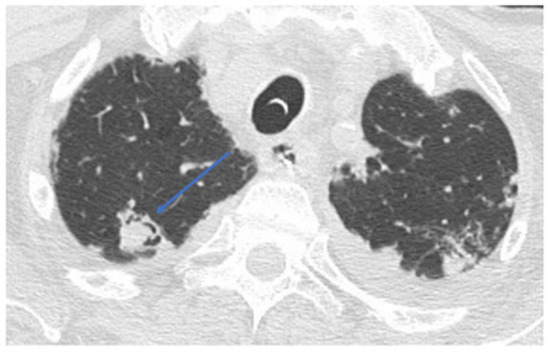

2. Case